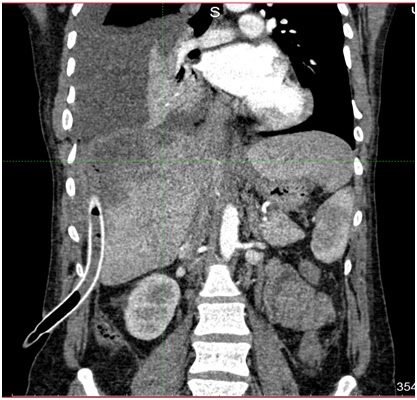

2. рис1б мскт | |

3. рис 2а мскт | |